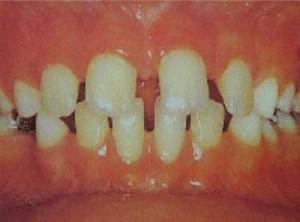

儿童牙齿稀疏一般在2.5-6岁左右,这时口内一般是乳牙,如果患儿牙齿数目、形态、大小正常,同时颌骨发育正常,牙列中出现散在的间隙,看似牙列稀疏,然而这一般是正常的。此有利于恒牙的正常萌出,临床上一般毋需矫治。如果牙体态小,颌骨形态正常;口内先天缺牙,颌骨形态正常;牙体形态正常,颌骨过大等,其往往造成牙列稀疏,此为疾病的征象,需加以矫治。

从6岁至12岁左右,此年龄段内,口内乳恒牙同时存在,这一时期牙列稀疏不常见,临床上常见到的乳牙早脱或恒牙迟萌以及由于唇系带附离异常所致的牙间间隙,此一时期只要针对病因,对症矫治,常可收到较好矫治效果。

牙列稀疏易于嵌塞食物而损伤牙周组织,引起牙龈炎,牙周炎,同时易于龋变。严重者可影响患者的容貌美观,造成心理精神障碍。此病及早根据引起牙列稀疏的原因,进行不同方法的矫治。